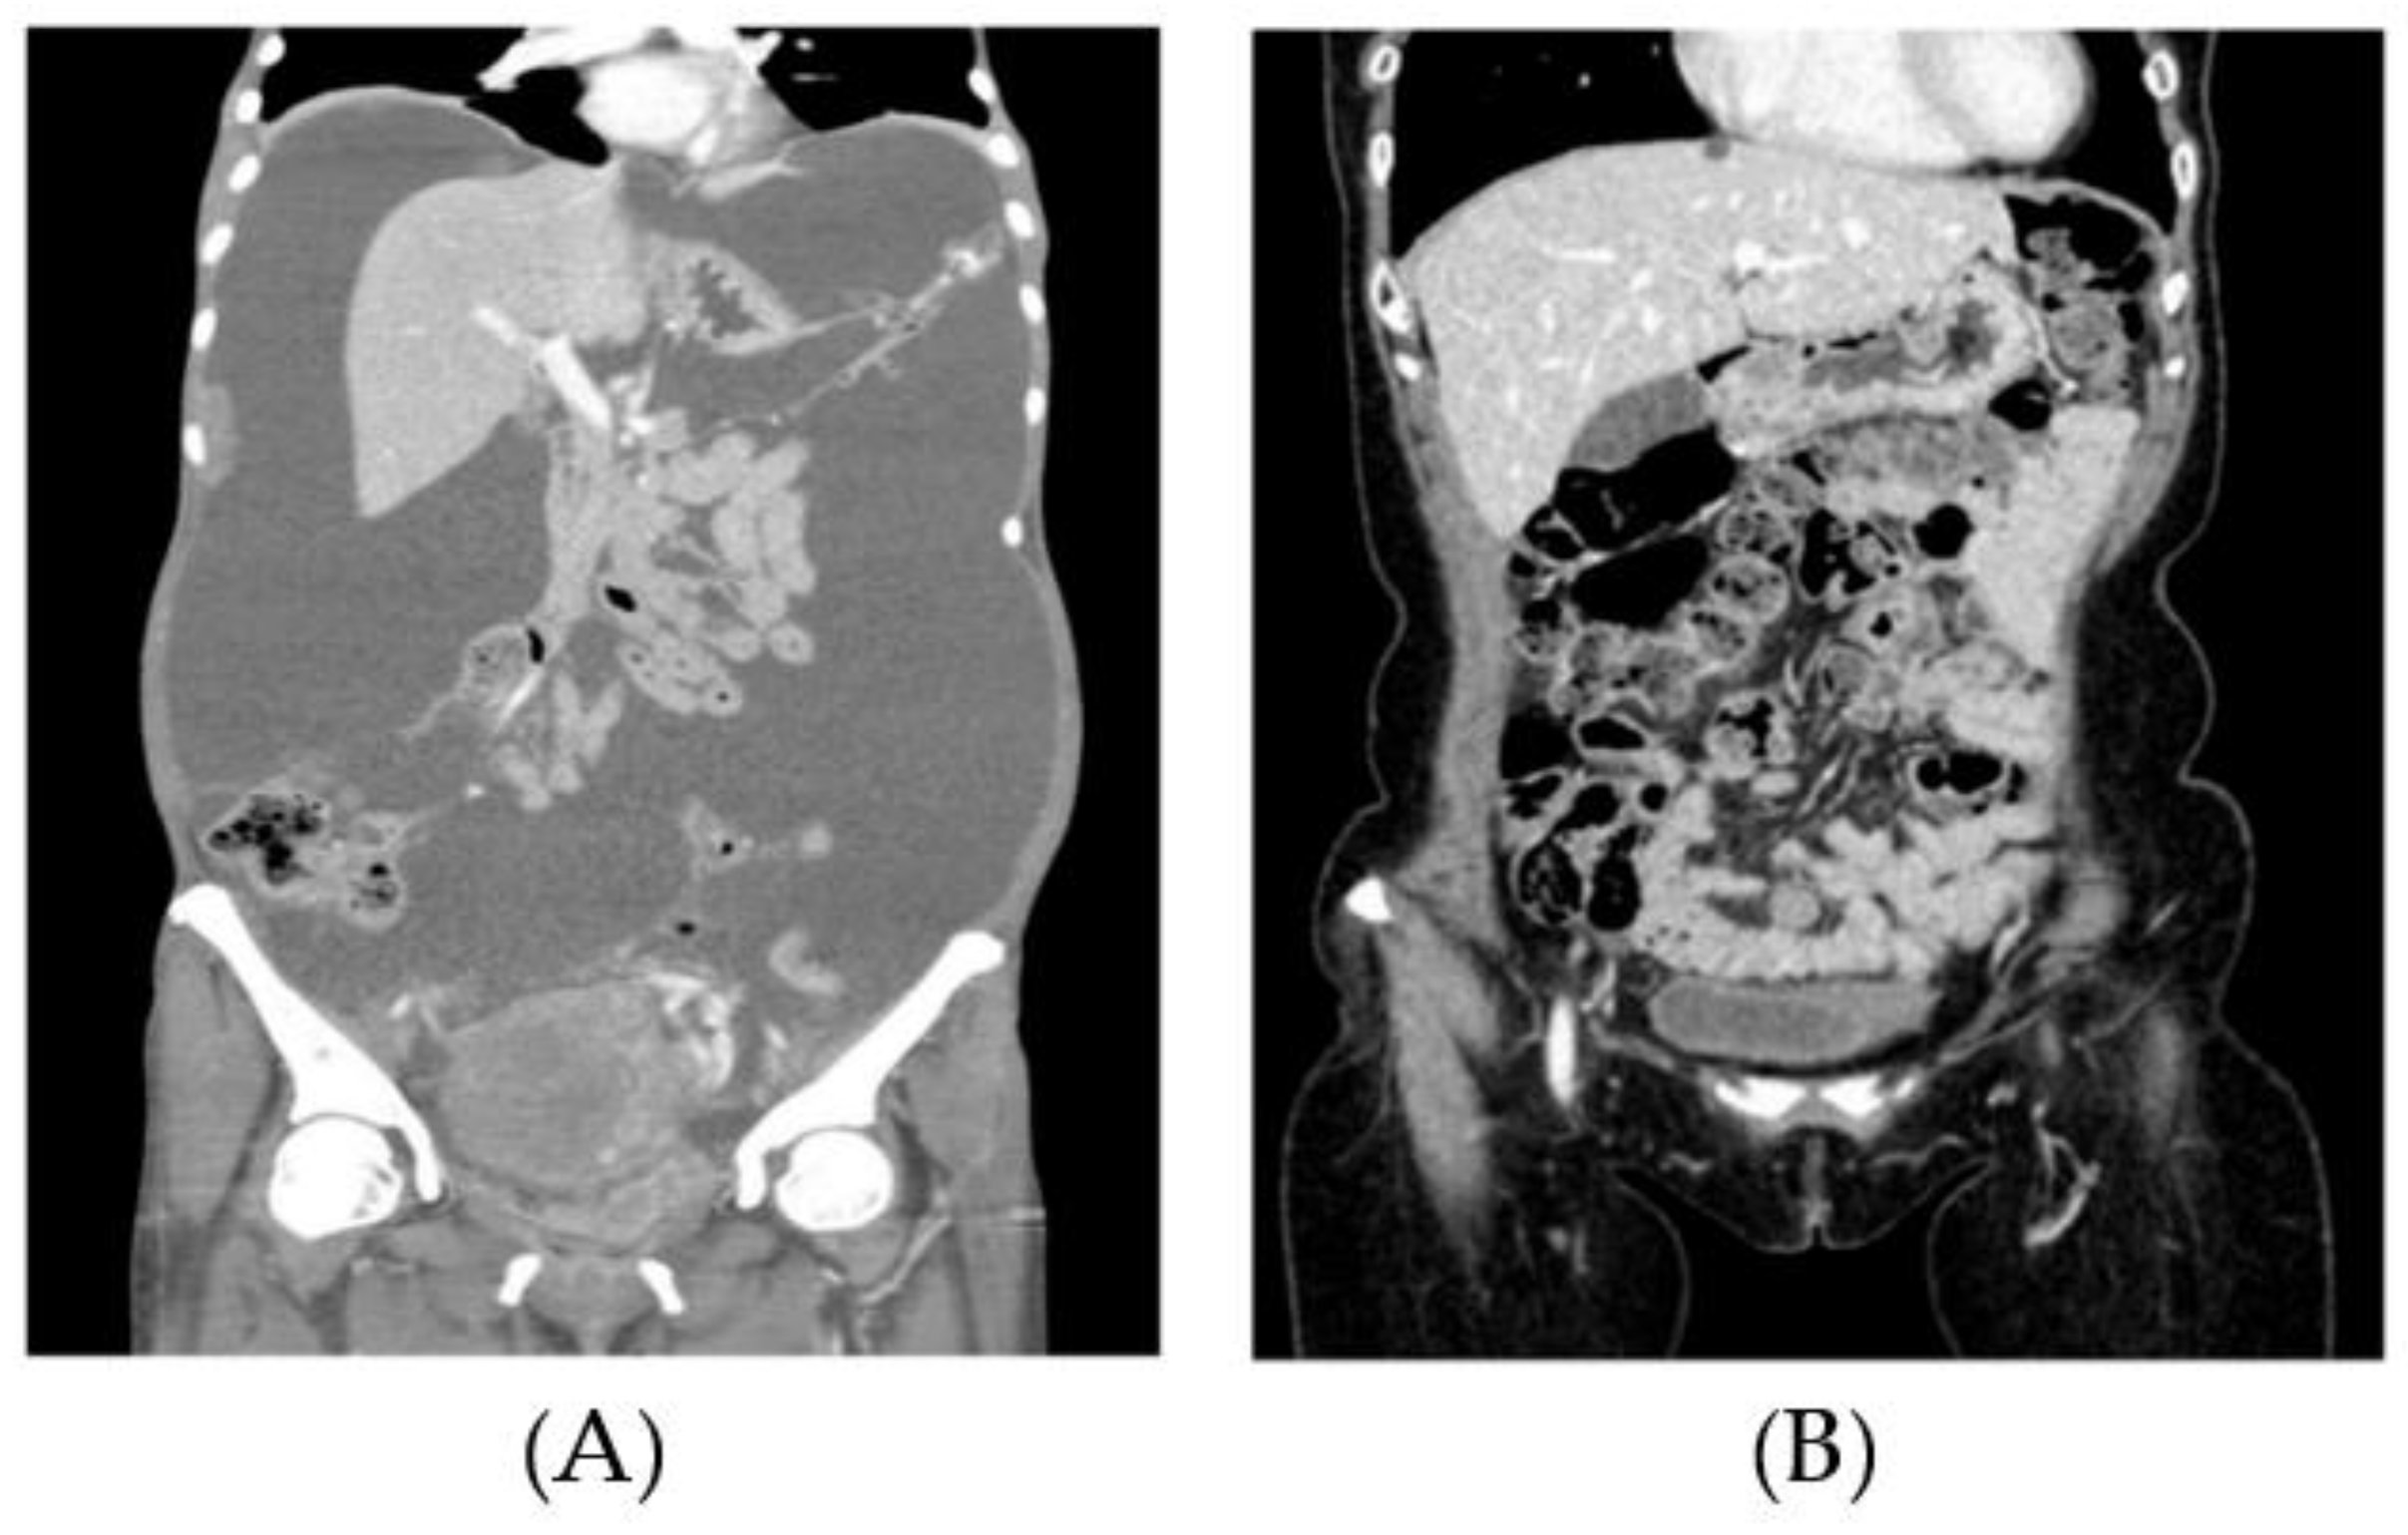

| CT | Computed tomography |

- Budak, Ü.; Guo, Y.; Tanyildizi, E.; Şengür, A. Cascaded deep convolutional encoder-decoder neural networks for efficient liver tumor segmentation. Med. Hypotheses 2020, 134, 109431. [Google Scholar] [CrossRef]